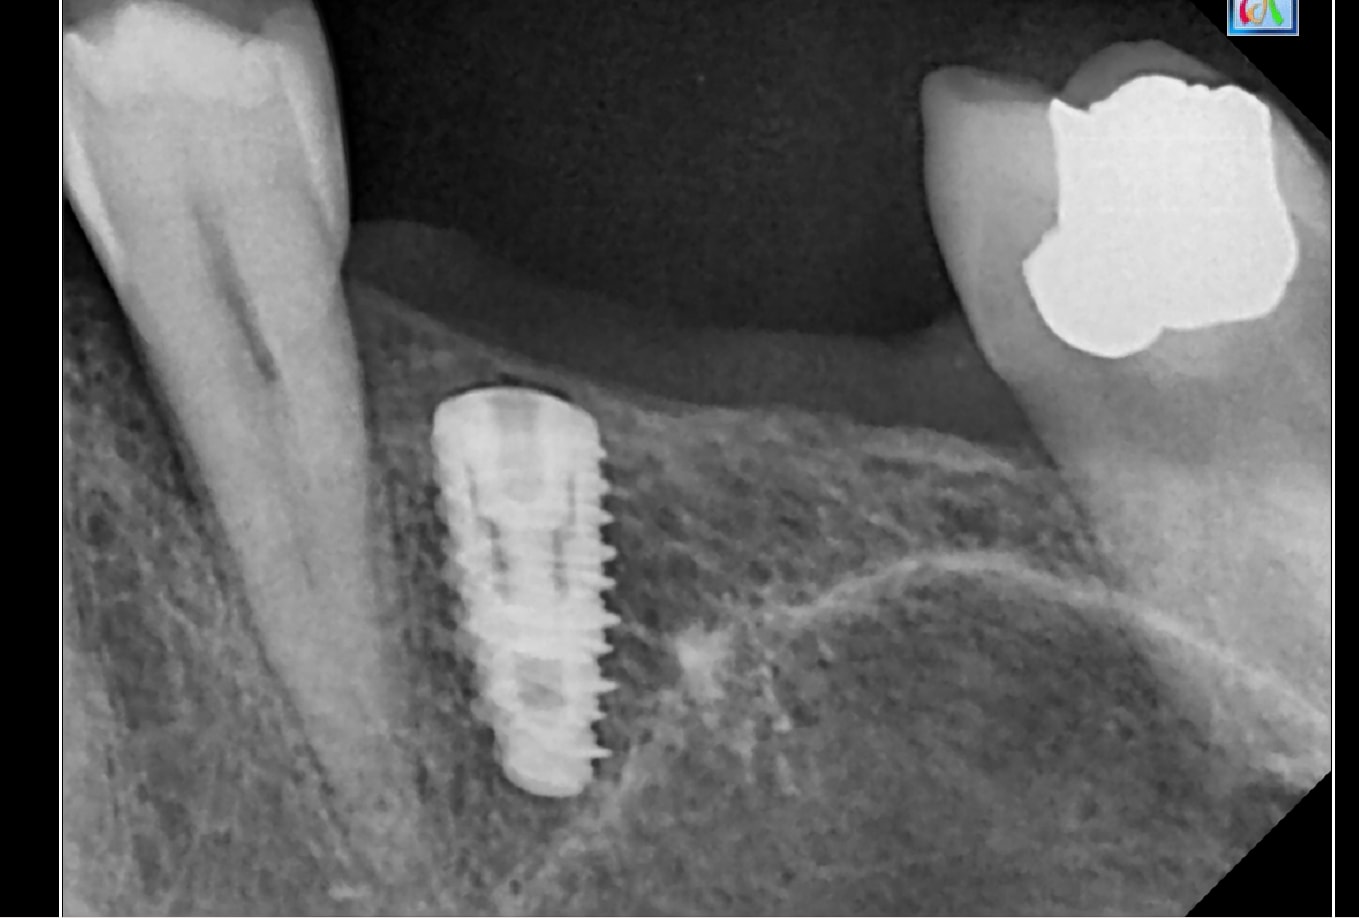

Hello pouvez vous me dire la marque des implants

manque la moitié des informations.....(manque la moitié des implants....)